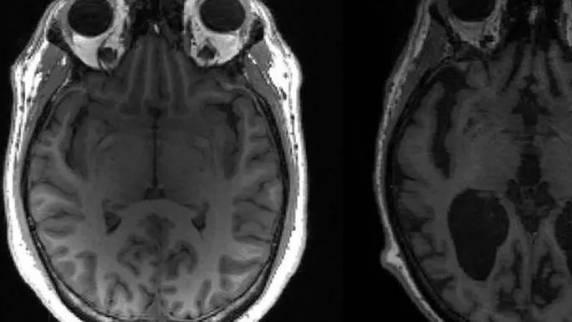

Pesquisadores do Instituto de Pesquisa de Demência do Reino Unido podem ter feito uma importante descoberta sobre a morte de neurônios provocada pela doença de Alzheimer. Em um artigo publicado na revista Science, a equipe associou as proteínas anormais que se acumulam no cérebro com a “necroptose”, uma forma de suicídio celular. As informações são da BBC Brasil.

O grupo reúne cientistas do Reino Unido e da Bélgica. Eles consideram que as recentes descobertas são “excitantes”, já que abrem caminho para novas ideias para o tratamento do Alzheimer. Até então, pouco se sabia sobre características-chave da doença, que incluem a perda de células cerebrais (os neurônios) e um acúmulo de proteínas anormais chamadas amilóide e TAU.

Agora, porém, os pesquisadores do Instituto de Pesquisa de Demência do Reino Unido acreditam que a amilóide anormal começa a se acumular nos espaços entre os neurônios, levando a uma inflamação cerebral que é nociva para essas células e passaria a mudar sua química interna.

Assim, começariam a surgir emaranhados de TAU e teria início a produção de uma molécula chamada MEG3, que provoca a morte das células cerebrais por “necroptose”. A “necroptose” é um dos métodos que o corpo humano normalmente usa para eliminar células indesejadas à medida que células novas são produzidas.